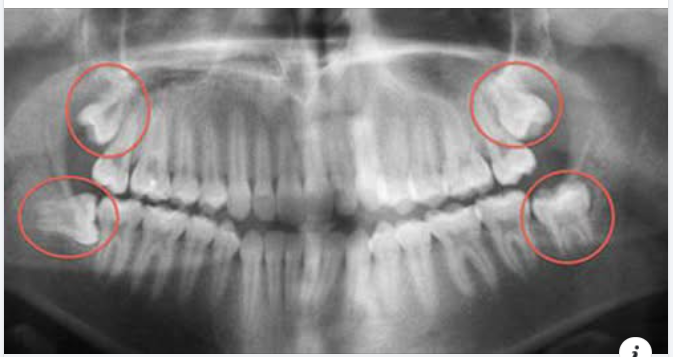

Nhổ răng khôn không đơn thuần là rút chiếc răng ra khỏi xương hàm, mà nó phức tạp hơn, đặc biệt nếu nó bị mọc kẹt.